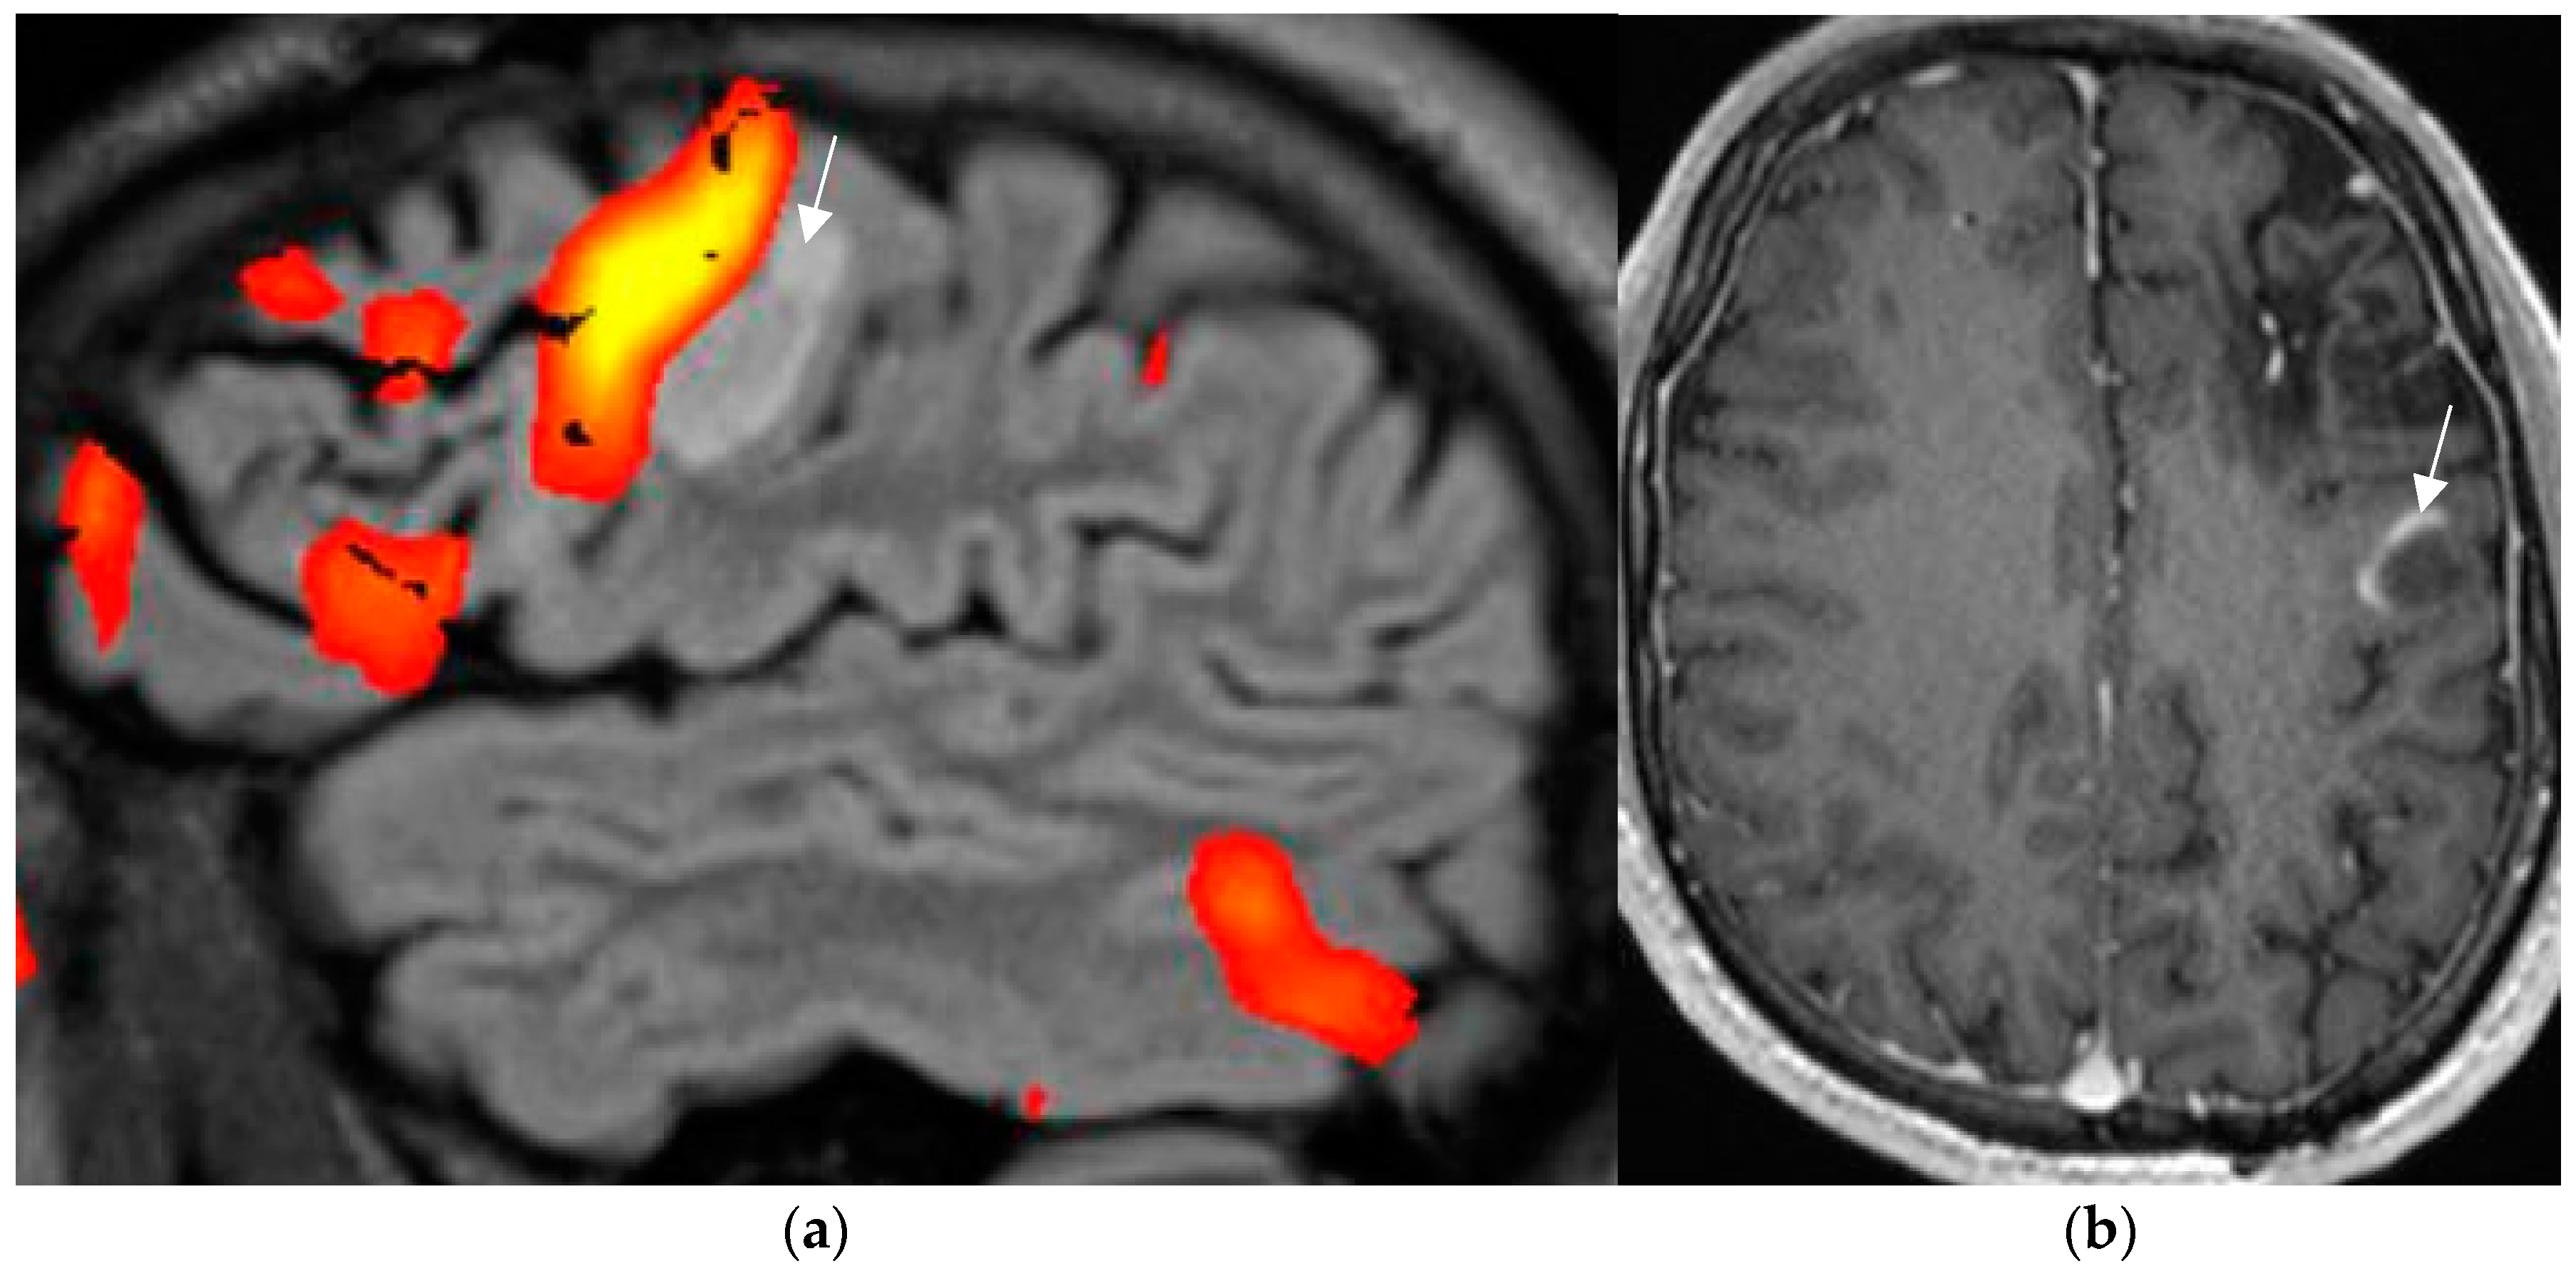

Postsurgical pathologic analysis of specimens of lesions missed by a negative brain MRI—even when performed using an epilepsy specific protocol—disclosed focal cortical dysplasia (FCD), hamartia, gliosis, and hippocampal sclerosis as the most common entities (Figure 1) [62].

Figure 1.

Histologically confirmed FCD I depicted by abnormal deep and straight left. collateral sulcus with a slight blurring of the gray–white matter junction on the FLAIR image. (a) (1.7 mm) and signal hyperintensity of the cortical border. Reduction of adjacent parahippocampal white matter (white arrow on MP2RAGE sequence) (b) slice thickness 0.9 mm. The hippocampus displays a mild signal increase on the FLAIR image (without atrophy) as a sign of dual pathology. Both lesions were missed on prior 1.5 T examination in a patient with left temporal lobe epilepsy.

4.2. A Standardized Epilepsy Specific Protocol Provides Superior Diagnostic Yield

A comprehensive epilepsy-targeted MRI protocol is the key factor to identify, localize, and characterize an epileptogenic lesion (Figure 1). The neuroimaging task force of the ILAE advises the “Harmonized Neuroimaging of Epilepsy Structural Sequences” (HARNESS-MRI) protocol that encompasses three “core” sequences: iso-tropic submillimetric FLAIR and 3D T1 images and high-resolution 2D T2 sequences to be performed soon after the first seizure [64].